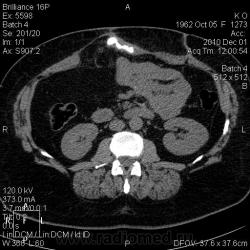

Свищи передней брюшной стенки. КТ.

Женщина 1962 г.р. В анамнезе псевдокиста поджелудочной железы, прооперирована около 6 мес назад. Фистуло-КТ. И красавица грыжа.